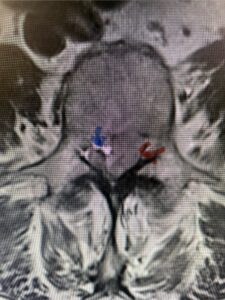

Fig. 3a : Sagittal T2-weighted lumbar MRI demonstrating a massive L4-5 disc herniation with superior migration behind the L4 vertebral body and taking up most of the left side of the spinal canal (red arrow) Note the slight grade one spondylothesis at L4-5 (blue dash). Notice the severe compression of the thecal sac (blue arrow) by the large left sided disc herniation (red arrow)

Fig. 3b: Axial T2-weighted lumbar MRI demonstrating severe compression of the thecal sac (blue arrow) by the large left sided disc herniation (red arrow) taking up most of the left side of the spinal canal (red arrow)